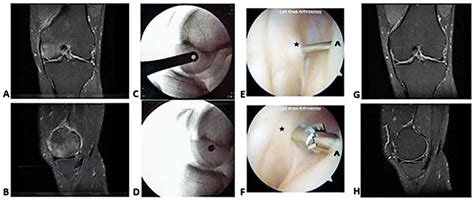

Magnetic Resonance Imaging (MRI) Offers detailed images of the bone marrow and surrounding tissues, making it the gold standard for diagnosing bone marrow edema.

In some cases, a biopsy of the bone marrow may be necessary to rule out other conditions, such as infections or tumors.